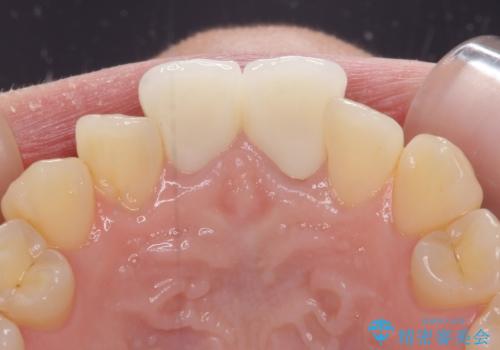

2本同時に処置したことで、形や色調をそろえることができ、自然な口元になりました。